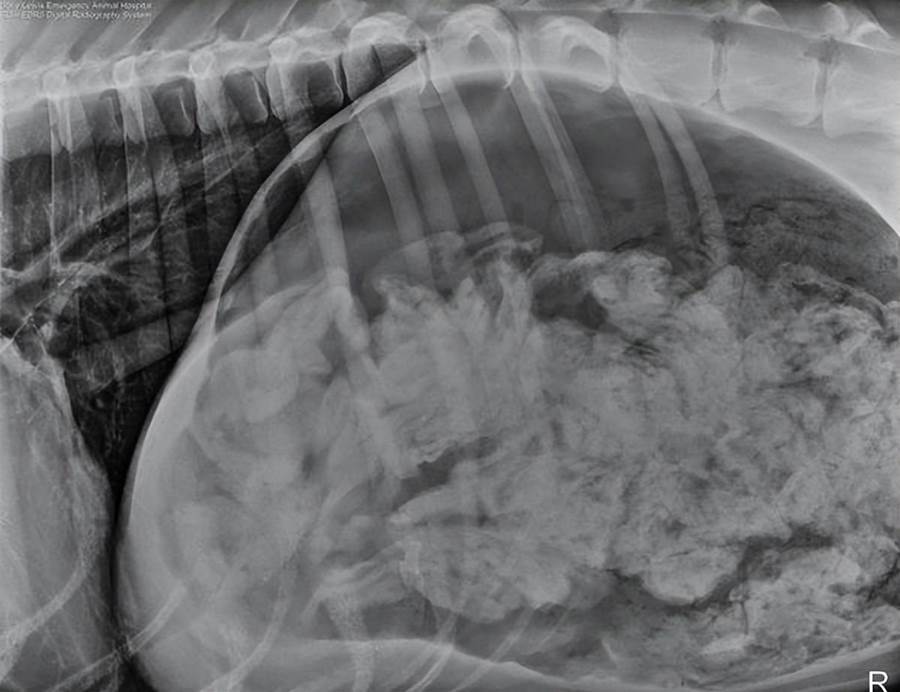

21:一只吞下了43只襪子后的大丹犬。